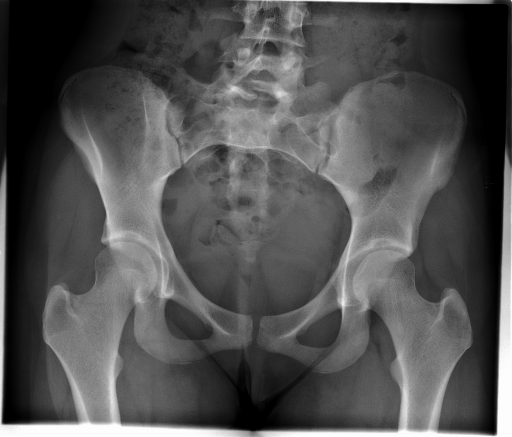

Image Dataset – The Image Retrieval in Medical Applications (IRMA) 2009 database is a collection of 14,410 x-ray images that have been randomly collected from daily routine work at the Department of Diagnostic Radiology of the RWTH Aachen University (Fig. 2). The downscaled images were collected from different ages, genders, view positions, and pathologies [33]. Each image in the dataset has an IRMA code. According to these codes, 193 classes are defined according to 2008 IRMA codes. The IRMA code comprises four axes with three to four positions each: 1) the technical code (T) (modality), 2) the directional code (D) (body orientations), 3) the anatomical code (A) (body region), and 4) the biological code (B) (the biological system examined). The complete IRMA code consists of 13 characters TTTT-DDD-AAA-BBB, with each character in . As many as 12,677 images are separated for training. The remaining 1,733 images are used as test data. In this project, the IRMA 2009 dataset has been used with specified 2008 IRMA labels (consisting of 193 classes) for retrieval purposes. Otherwise, same dataset is utilized with general 2005 IRMA labels (consisting of 57 classes) for classification purpose. 2005 IRMA labels are more general than 2008 IRMA labels because it has been made of 6 characters from top of hierarchical classes, TT-D-AA-B. In 2009 dataset, each image can not have been coded according to 2005 IRMA coding regularity. A total number of 12,631 images from training set and 1,639 images from testing set have 2005 IRMA codes. For this reason, SVM classification is implemented on corresponding images.